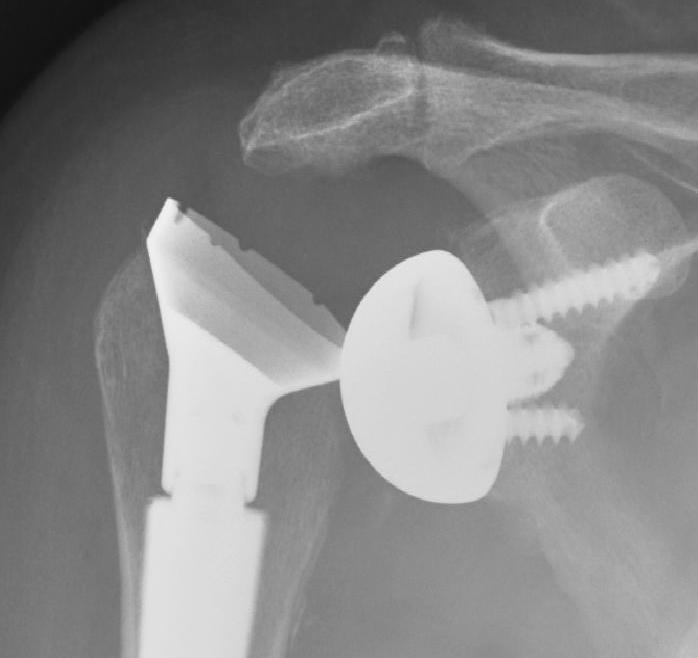

Reverse TSR NotchingGlenoid fracture

Humeral shaft fractures

Hum shafthum shaftHum shaft

Stable humeral component treated with ORIF

hum #Hum #Hum #

Unstable humeral component